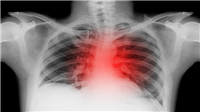

يوجد العديد من أمراض القلب الصامتة التي يصعب الكشف عنها، ولكن يُمكن الكشف المبكرعن امراض القلب حتى وإن كانت صامتة من خلال إجراء عدة فحوصات، تابع قراءة المقال الآتي لتتعرف على الفحوصات التي تساعد في الكشف المبكر عن امراض القلب:

تحاليل تساعد في الكشف المبكر عن امراض القلب

يوجد تحاليل يجب إجراؤها من أجل الكشف المبكر عن امراض القلب خصوصًا إذا تواجد أي من العوامل التي تزيد من خطورة الإصابة بأمراض القلب، والتي تشمل على الآتي:

تشخيص تضخم القلب

هناك اختبارات عدة تساعد في تشخيص الإصابة بتضخم القلب، ومنها الاتي:

مخطط كهربية القلب لرصد النشاط الكهربائي في القلب وتشخيص الإصابة بتسارع في نبضات القلب.

مخطط صدى القلب الذي يستخدم الموجات الصوتية لتشخيص مشاكل حجرات القلب.

تحاليل الدم.

اختبار الجهد.

تصوير الصدر بالأشعة السينية.

التصوير المقطعي المحوسب (CT).

التصوير بالرنين المغناطيسي (MRI).

قسطرة القلب.